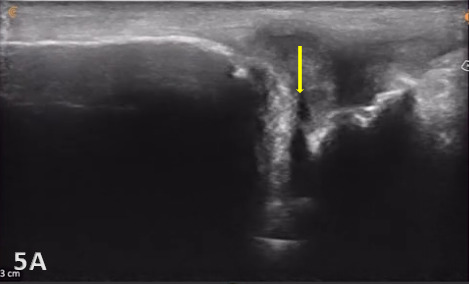

Direct ultrasound findings of TFCC injury include:

Hypoechoic or anechoic cleft seen within the normal fibrillar pattern of a normal TFCC.

Irregular or disrupted margins of the articular disk.

Thinning or fissuring of the TFCC indicates a partial-thickness tear.

Abnormal thickness of the TFCC, such as thinning (degeneration) or thickening (edema or chronic overuse), may be seen as pathology.

A complete disruption of the continuity of fibers of ligaments or the disk with fluid extending into the joint would indicate a complete full-thickness tear of the TFCC.

Associated joint effusion and/or synovitis (synovial hypertrophy) and cysts. Joint effusion will appear as anechoic or hypoechoic fluid within the DRUJ or TFCC area. Joint effusion is somewhat compressible and mobile when transducer pressure is applied to the area. This is different from synovitis, which appears as hypoechoic or isoechoic, non-compressible tissue within the joint recess. Lastly, a ganglion cyst will appear as a well-defined, round or lobulated cystic structure with anechoic or hypoechoic internal contents. The cyst typically has a small, smooth wall and exhibits posterior acoustic enhancement. These cysts will typically be minimally or non-compressible and painful.